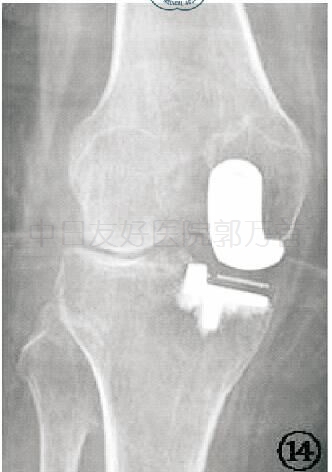

X线片九:并发症之活动垫片脱位

X线检查可以发现衬垫移位的位置,同时还可能提示造成移位的原因,如骨赘、骨水泥残留、金属假体移位等。